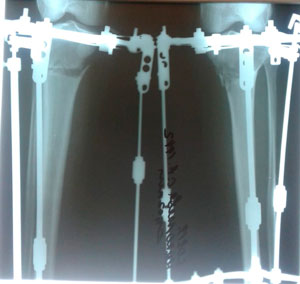

Дата операции - 12.07.2019г.

Дата снятия аппаратов - 17.10.2019г.

Срок сращения - 95 дней.